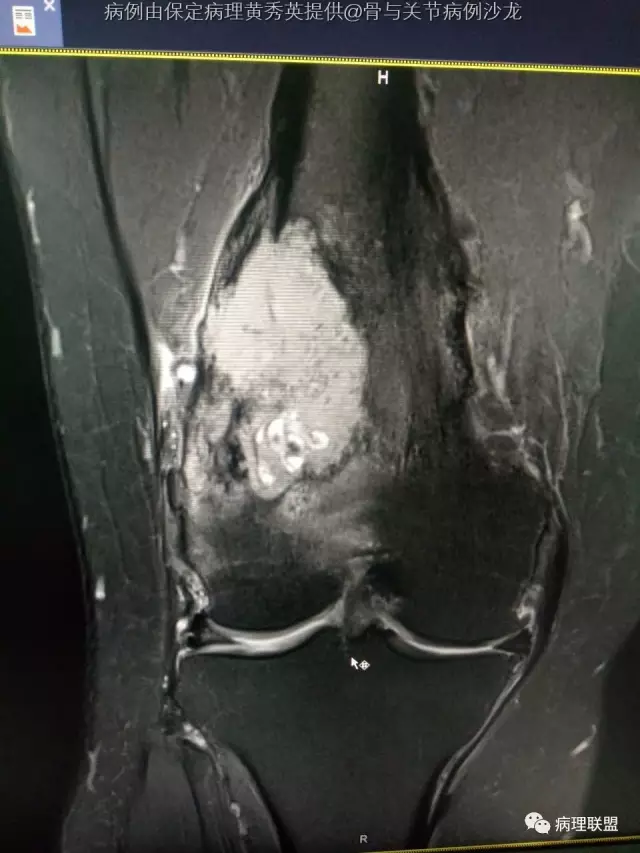

女67岁,股骨下端肿物约6cm,(病例由保定病理黄秀英提供,致谢!)